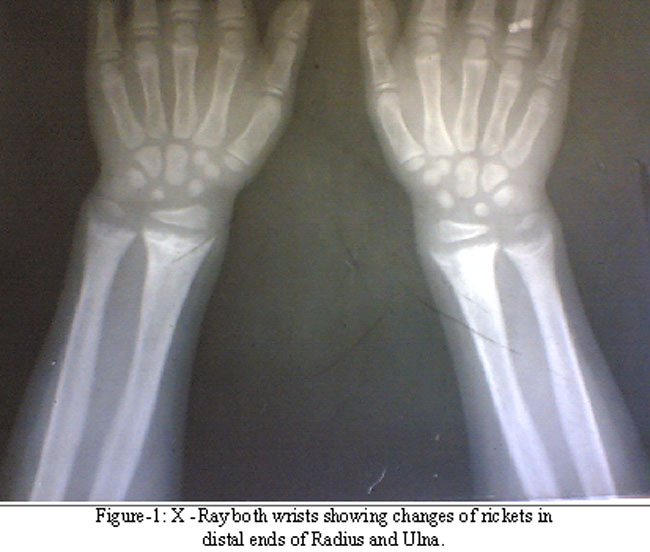

A -15-year girl was evaluated at the age of 5 years for lower limb deformities. She was the second child of her non consanguineous parents, was born full term and had no perinatal insult. She had been weaned at appropriate age and had a normal physical and mental development. At age 4 years; her parents noticed deformities in her lower limbs. The child was diagnosed to have rickets and treated with 3.6 million units of vitamin D (six lac units weekly intramuscularly over a period of six weeks). There was no clinical or radiological evidence of improvement over the next one year. She was referred to the endocrinology for further evaluation. Examination revealed height of 105 cms [50th percentile by Indian Council of Medical Research (ICMR) standards] with upper segment to lower segment ratio of 1:1 and weight of 17 Kgs (50th percentile by ICMR standards). She had signs of rickets in the form of widening of wrists, rachitic rosary and knock knees. Investigations revealed normal complete blood count (CBC), liver and kidney functions. Bone function tests revealed a serum calcium of 8.9 mgs/dl, (normal value of 9.5-11.5mgs/dl), phosphorus of 4.3 mgs/dl (normal value of 5-7mgs/dl for her age) and alkaline phosphatase of 611U/L (normal value 30-120 in adults). X-ray wrist revealed changes of rickets (Figure-1), Pelvic x-ray revealed looser, s zones in superior and inferior pubic ramie. She was evaluated for non nutritional rickets. She had no evidence of renal tubular acidosis or Fanconi syndrome. Serum 25- hydroxy vitamin D was 100 ng/ml (normal value 8-80), 1, 25 dihydroxy vitamin D was less than 5 pg/ml (normal value16-65). Serum concentrations of 25-hydroxy vitamin D and 1, 25 dihydroxy vitamin D were measured by specific radioimmunoassay. In view of clinical and radiological evidence of rickets, no response to massive doses of vitamin D, high Serum 25- hydroxy vitamin D and undetectable 1, 25 dihydroxy vitamin D a diagnosis of pseudo vitamin D deficiency rickets was made. She was started on calcitriol 0.25 g/day and elemental calcium 500mgs/day. The patient was next seen after four months and had a marked clinical and radiological improvement (Figure-1).